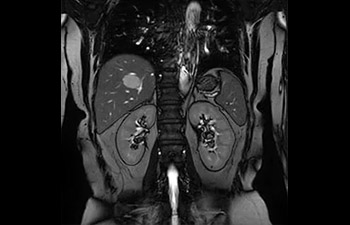

Tronco image

Hemangioma hepático.

con Compressed SENSE